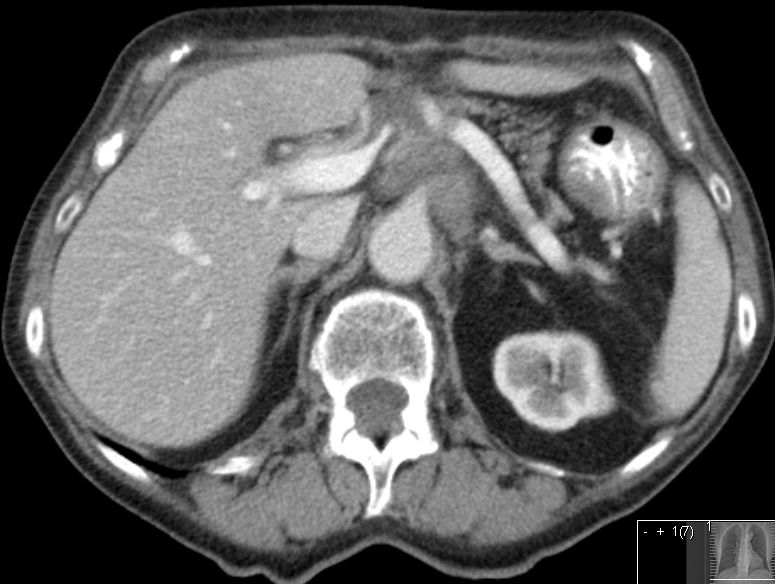

| Leber - Metastasierung | ![]() |

48-jähriger Mann mit hepatisch metastasiertem Pankreaskopf-Karzinom.

Histologische Sicherung vor 6 Monaten: schlecht differenziertes Adenokarzinom. Chemotherapie: FOLFOXIRI. Restaging: Progress. Leber mit Metastasen durchsetzt.![]() |